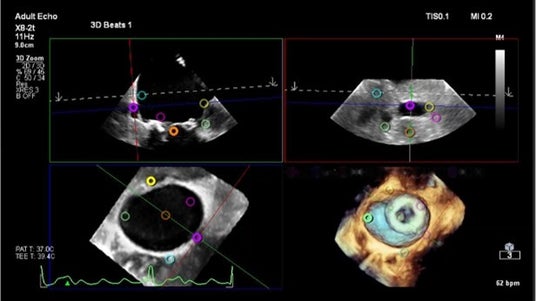

3. SHD領域でのワークフローの向上「3D Marker」

近年のSHD領域での心エコー図の役割はデバイスの発展とともに高まっています。Transcend Plusには3D Marker機能が搭載され、3DやMPR断面にマーカーを置くことが可能になりました。迅速な判断が求められる環境で、複雑な解剖の理解度を高められることが期待できます。